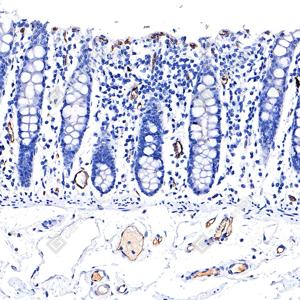

| IHC检测eNOS蛋白(货号 GB15086). 样品: 人结肠, 4%多聚甲醛 (货号G1101) 固定12-24小时. 抗原修复: 抗原修复仪(货号 ARI-4),Tris-EDTA抗原修复液(pH 9.0) (货号G1203), 水浴100℃, 25分钟. —抗: 1: 1000稀释, 4℃ 孵育过夜. 二抗: S-vision免疫组化多聚二抗(山羊抗兔),即用型 (货号G1302), 室温孵育20分钟. |